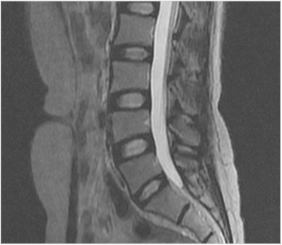

추간판의 변성

정상적인 추간판의 형태

변형된 추간판의 형태